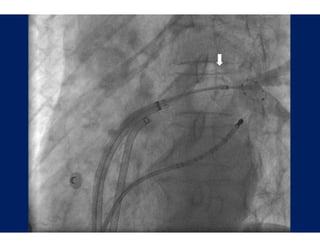

Li ewire™ TC

Live i

Ablatio Catheters

on

Diagnostic Catheters

Guiding Introducers

Specialty Spiral Catheters

Introducers        Steerab Diagnostic

ble

Catheters

C

Wide Area Circum

mferential Ablation

Oral et al.: Circulat

tion 2003;108;2355-60

Procedural Success

P    d al S

Elimination of Pulmo

onary Vein Potentials

During A

Ablation

Li ewire™ TC Live i Ablatio Catheters on Diagnostic Catheters Guiding Introducers Specialty Spiral Catheters Introducers Steerab Diagnostic ble Catheters C

Wide Area Circum mferential Ablation Oral et al.: Circulat tion 2003;108;2355-60

• 71.

Procedural Success P d al S Elimination of Pulmo onary Vein Potentials During A Ablation